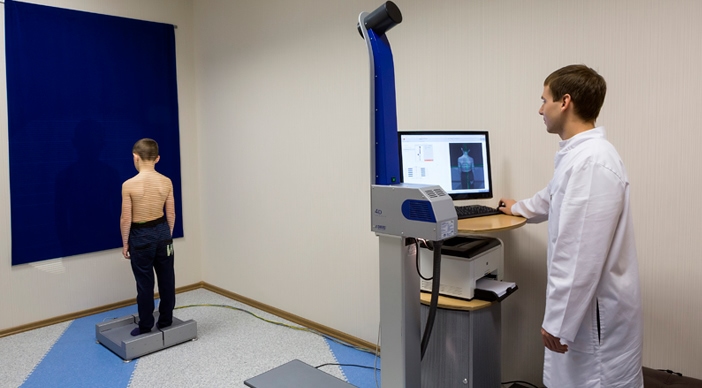

Оптическая диагностика позвоночника Diers: изображения и технологии

Раздел: Мир в картинках